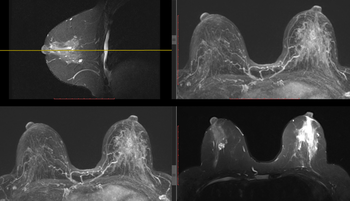

L’imagerie médicale regroupe des examens qui permettent d’obtenir des images de l’intérieur du corps. Ces images aident les professionnels de santé à poser un diagnostic, à suivre une maladie ou à évaluer un traitement.

Disposant de toutes les modalités d'examen (Imagerie par Résonnance Magnétique (IRM), scanner, artériographie diagnostique et interventionnelle, échographie, mammographie, radiologie générale) et fort d'une équipe de 30 radiologues et 4 médecins spécialistes en formation, le Service d'Imagerie médicale de la Citadelle exerce son activité sur 4 sites (Citadelle, Herstal, Laveu et Valdor).